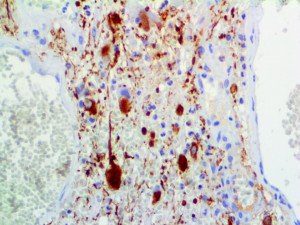

It is the ICU physician who is most likely to witness one of the deadliest manifestations of the abnormal immunological response, the cytokine storm syndrome (CSS). This response is also referred to by some as the cytokine release syndrome (CRS). CSS is characterized by continuous activation and expansion of macrophage and lymphocyte populations, which secrete large amounts of cytokines, causing the cytokine storm. This massive cytokine release is akin to hemophagocytic lymphohistiocytosis (HLH) disease, a syndrome characterized by initial unchecked and persistent activation of cytotoxic T lymphocytes and NK cells.

Clinical and laboratory manifestations of HLH include fever, enlarged liver and/or spleen, neurologic dysfunction, coagulopathy, liver dysfunction, cytopenias (i.e., low levels of erythrocytes, leukocytes, and/or platelets), hypertriglyceridemia, hyperferritinemia, hemophagocytosis, and eventually diminished NK cell activity as the immune system becomes progressively paralyzed. HLH can be familial (primary HLH) or secondary to another disease process (sHLH), such as rheumatic disease, in which it is referred to as macrophage activation syndrome (MAS, characterized by elevated ferritin).